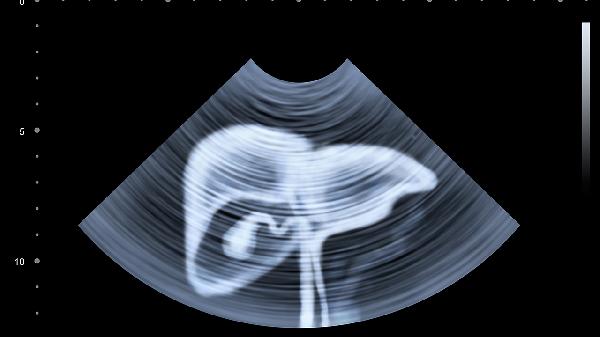

每年檢查肝功能、肝臟超聲和甲胎蛋白,乙肝表面抗原陰性者建議接種疫苗。已有肝病患者需每3-6個(gè)月監(jiān)測(cè)肝纖維化指標(biāo)。40歲以上人群應(yīng)篩查肝癌標(biāo)志物,有家族史者需加強(qiáng)影像學(xué)檢查。發(fā)現(xiàn)轉(zhuǎn)氨酶升高或占位性病變應(yīng)及時(shí)專科就診。